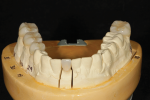

After the prosthodontist delivered the fixed prostheses with minimal adjustment, he

created rest seats on abutment teeth Nos. 2 and 6 before making a final impression for an RPD framework. The master cast was then sent to the laboratory of the first author, Mr. Kolbeck, who fabricated an RPD framework with a cobalt chromium alloy (Vitallium 2000 Plus®, Dentsply Sirona, dentsplysirona.com) (Figure 15).

Upon receiving the framework, the prosthodontist tried it in the patient's mouth to ensure a passive fit with the angle correcting rings (Sphero Block Micro®) (Figure 16 and Figure 17). After the framework's fit was verified, he mounted the RPD framework on the articulator to set anterior denture teeth (Creapearl®, Willi Geller Creation, creation-willigeller.com).